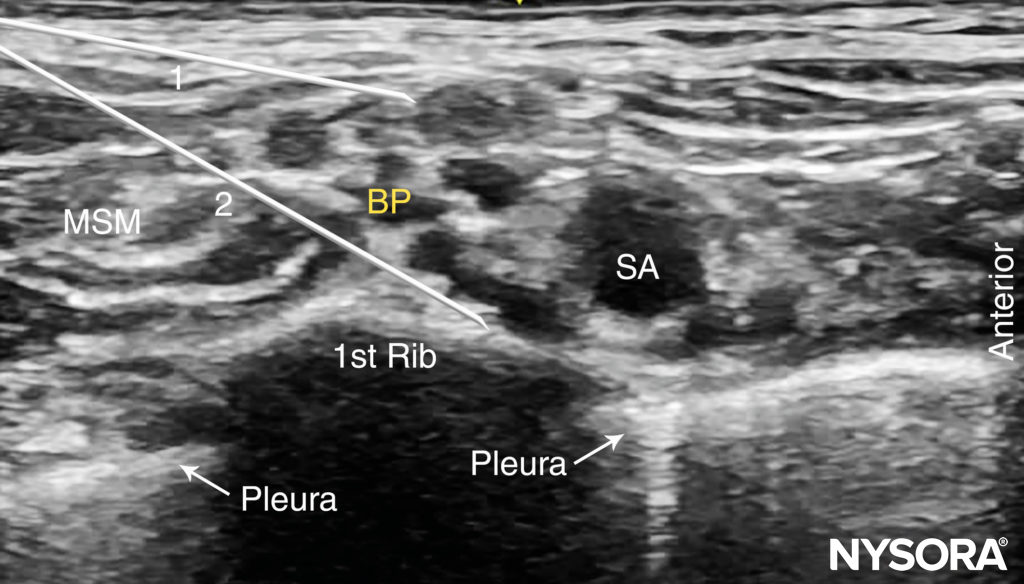

Using a 25- to 27-gauge needle, 1–2 mL of local anesthetic is injected into the skin 1 cm lateral to the transducer to decrease discomfort during needle insertion. To avoid inadvertent puncture of and injection into the brachial plexus, the needle should not be initially inserted deeper than 1 cm. The distribution of local anesthetic via small-volume injections is observed as the needle advances through tissue layers (hydro-localization); small-volume injections are used to avoid inadvertent needle insertion into the brachial plexus. The nerve block needle is then inserted in plane toward the brachial plexus, in a lateral-to-medial direction (Figures 5 and 6).

FIGURE 6. Supraclavicular brachial plexus nerve block: needle path and two separate injections required for nerve block of the brachial plexus. Two needle positions (1 and 2) are used to inject local anesthetic within the connective tissue sheath (arrows) containing the brachial plexus (BP).

Nerve stimulation (0.5 mA, 0.1 msec), is often associated with a motor response of the arm, forearm, or hand. Note, however, that motor response may be absent despite accurate needle placement. Insertion of the needle into the sheath is often associated with a palpable “pop.” After careful aspiration, 1–2 mL of local anesthetic is injected to confirm proper needle placement. When the injection displaces the brachial plexus away from the needle, an additional advancement of the needle 1–2 mm closer to the plexus may be required to accomplish adequate local anesthetic spread (Figures 7, 8, and 9). When the injection of local anesthetic does not appear to result in a spread around the brachial plexus, needle repositioning may be necessary. Typically, 20–25 mL of local anesthetic is required for adequate nerve block. It has been suggested that lower volumes can be used in older patients. (see Figure 7). Supplementary video related to this nerve block can be found at Ultrasound-Guided Supraclavicular Brachial Plexus Nerve Block Video.